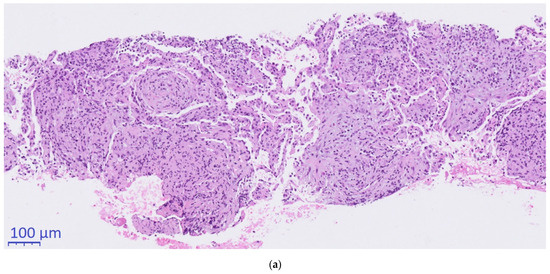

Histopathological conciliary reevaluation with additional application of Grocott’s methenamine silver stain on the resected lymph nodes detected micrometric (~5µm) ovoid elements typical of H. capsulatum in the necrotic areas (Figure 2c), which were not visible in the PAS stain. Although amplification of DNA for sequencing of the internal transcribed spacer region from paraformaldehyde-fixated biopsy tissue, serology and urinary antigen was negative for H. capsulatum (day +63), pulmonary histoplasmosis was diagnosed based on the pathognomonic histomorphological results.

Figure 2.

Histopathological evaluation. (a): 10×. (b): 2×. (c): 40×., (a,b): Hematoxylin & Eosin. (c): Grocott’s methenamine silver stain. (a) CT-guided core needle biopsy of the pulmonary mass showing organizing pneumonia (b) Supraclavicular lymph-node presenting with necrotizing granulomas (c) Typical ovoid Histoplasma capsulatum yeasts stained in black and thus made visible using Grocott’s methenamine silver staining.